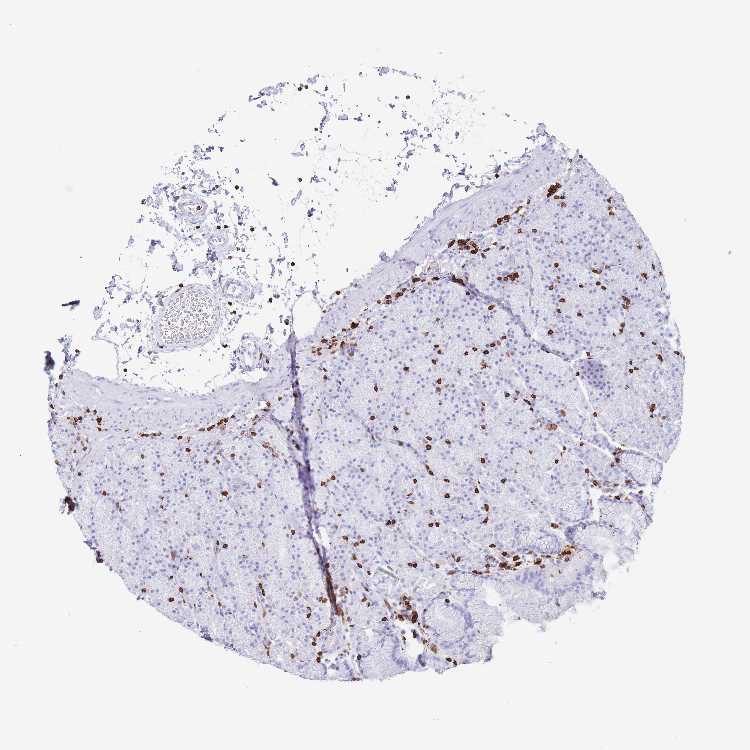

TISSUE PRIMARY DATA STOMACH Show tissue menu

STOMACH 1 - Antibody stainingi

Antibody staining in the annotated cell types in the current human tissue is reported as not detected, low, medium, or high, based on conventional immunohistochemistry profiling in selected tissues. This score is based on the combination of the staining intensity and fraction of stained cells.

Each image is clickable and will lead to virtual microscopy that enables deeper exploration of all samples and also displays staining intensity scores, fraction scores and subcellular localization as well as patient and tissue information for each sample.

Antibody HPA051132Antibody CAB046473

Glandular cells Not detectedNot detected